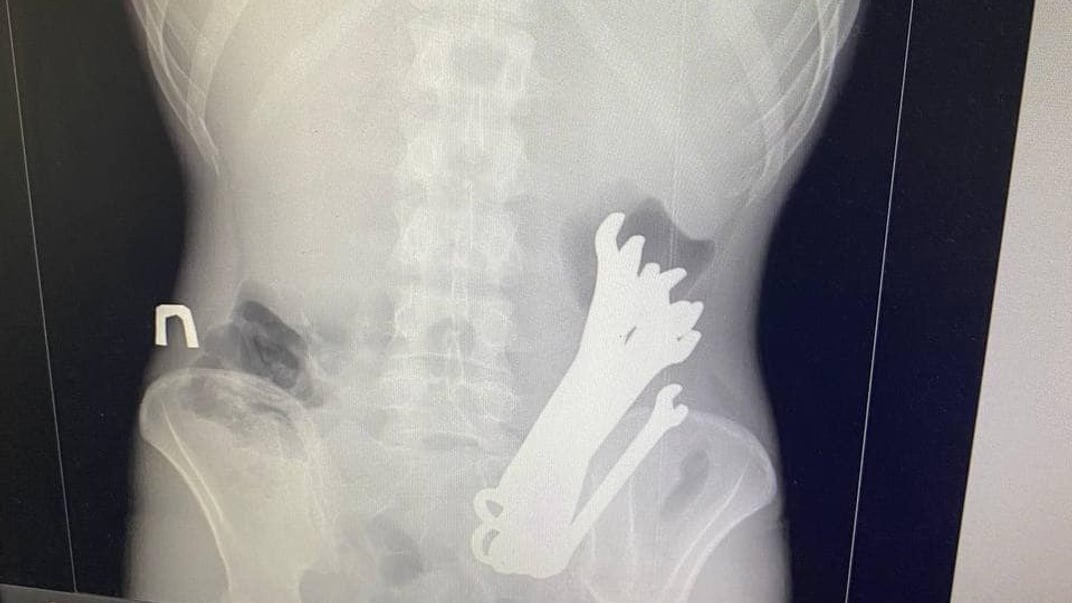

Медики Черкаської обласної лікарні розповіли про випадок надання допомоги пацієнту, всередині якого було 6 гайкових ключів.

Інцидент стався в серпні. Пацієнта «К.» госпіталізували з флегмоною шиї, розривом стравоходу на рівні горла та середньої третини, тотальним медіастинітом, емпіємою плеври з правого боку, сторонніми тілами та опущенням шлунку.

Медики одночасно виконали кілька втручань — цервікотомію з лівого боку, правобічну торакотомію з медіастинотомією, верхньо-серединну лапаротомію, гастротомію з накладанням гастростоми.

Після 3 тижнів лікування хворого виписали з одужанням із відділення торакальної хірургії.